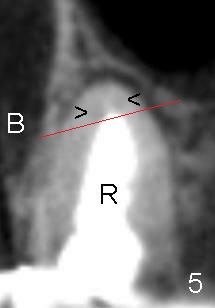

让我们顺着右上五(图四)长轴做个切面,显示这颗牙齿颊舌侧断面(图五:B:颊侧;R:根管充填),仿佛根尖有两个尚未被扩大冲洗充填的末端根管(箭头,导致根尖阴影没有消失),让我们再次沿着红线做个冠状断面,后者同样似乎显示两个根管(图六箭头)。